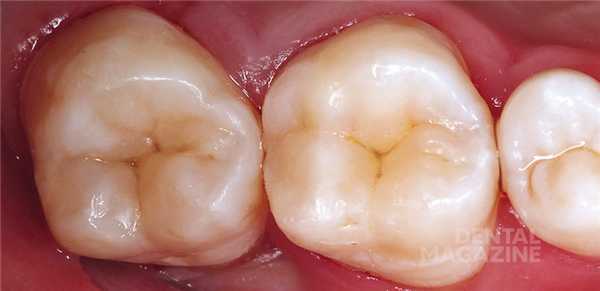

После этого, если есть желание, можно воспроизвести характеристики с помощью композитных красок. Вид после финишной отделки и полировки (рис. 10) .

Окклюзионная коррекция, как правило, минимальна или вообще отсутствует. Вид реставраций через двое суток (рис. 11) .